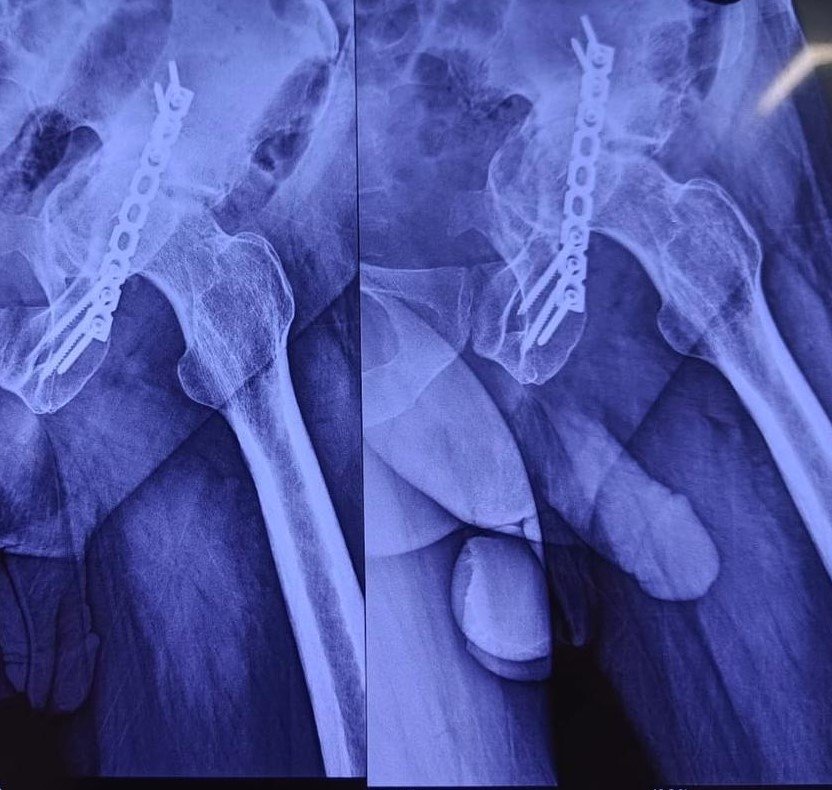

DHS Failure & Long Stem THR

AVN with Protrusio following Acetabular Fixation

Post-Op X-Ray